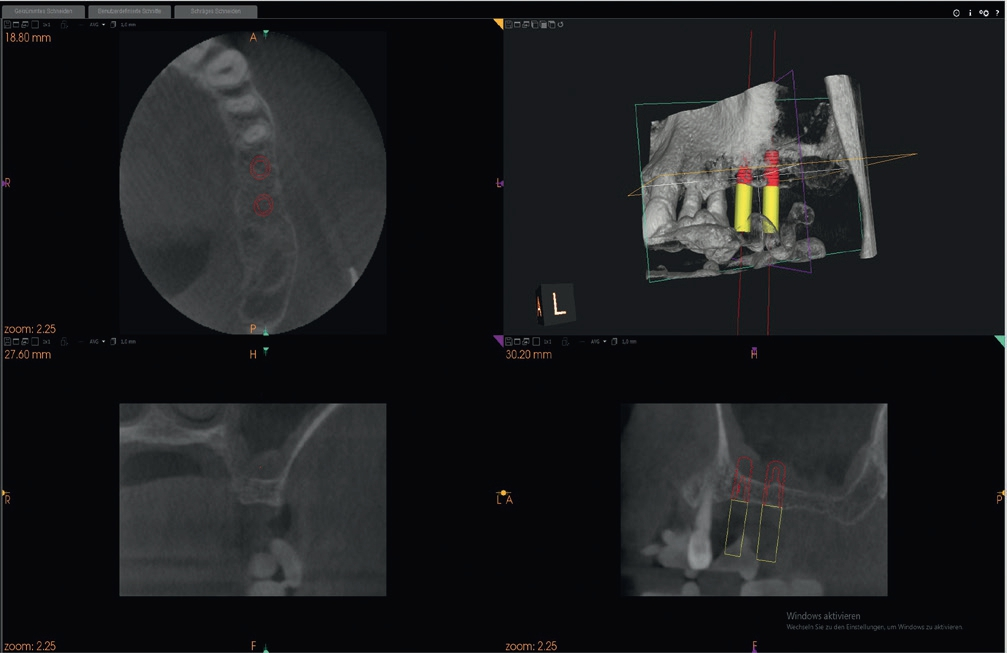

Bei dem behandelten Patienten wurde die Schneider-Membran angehoben, um das Knochenaugmentat zwischen dem respiratorischen Epithel der Kieferhöhle und dem Kieferhöhlenboden einzubringen. Hierbei wurde ein Gemisch aus autologem Eigenknochen und xenogenem Knochenersatzmaterial unterhalb der elevierten Kieferhöhlenmembran eingebracht und mit einer resorbierbaren Membran verschlossen, um ein gesteuertes Knochenwachstum (GBR) im augmentierten Bereich zu gewährleisten. Dieser Eingriff erfolgte im Rahmen einer Implantatplanung mit 3D-Technologie, die besonders bei einem dünnen Kieferknochen wichtige Dienste bei der Bestimmung des Restknochenangebots leistet.

3D-Technologie besonders bei komplexen Fällen hilfreich

Im vorliegenden Patientenfall zeigte das DVT ein vertikales Knochenangebot von ca. 4,0 mm, sodass im Hinblick auf Größe und Durchmesser bereits im Vorfeld eine Selektierung des zu verwendenden Implantattyps getroffen werden konnte. Ebenso konnte eine häufig anzutreffende knöcherne Septierung der Kieferhöhle ausgeschlossen werden. Ebenfalls sehr wichtig ist auch die RFA, die in diesem Fall besonders große Bedeutung hatte, da bei so marginalem Knochenangebot zunächst kein hoher Implantat- Knochen-Kontakt ermittelt werden kann.